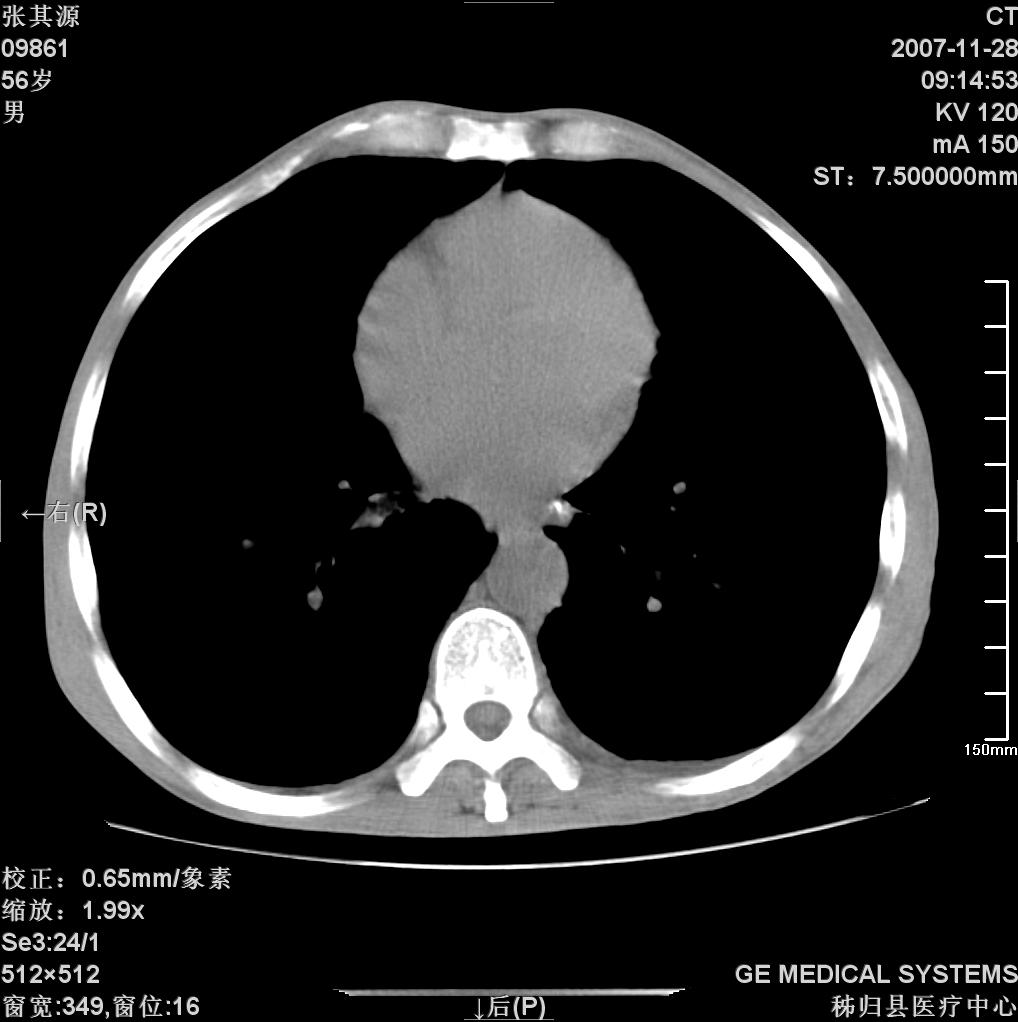

患者因阻塞性黄疸入院,发病前10天持续中等程度发烧.术前检查发现两肺弥漫性病变,请各位大虾会诊,除了考虑急性血源性肺结核外,还有其他什么疾病可能.

补充一下,该患者没有与尘肺相关职业史。请大家帮忙会诊一下,外科医生打算为其做胆总管肿瘤做手术的,现在在等我们的结果。谢谢各位了。

双肺多发粟粒样病灶,右肺胸膜下结节样病灶,气管前腔静脉后及隆突下均见肿大淋巴结,结合胆道肿瘤病史首先考虑转移。另外心影密度略低,时间格显示,是否有贫血?查明白再手术吧!